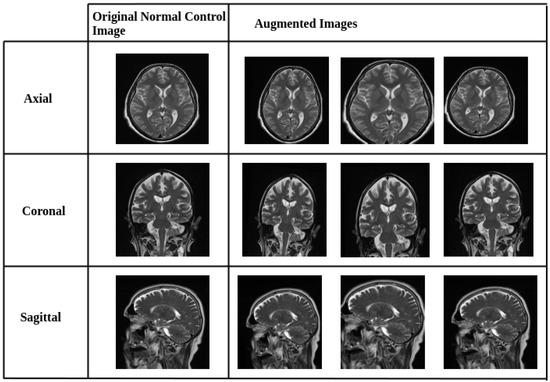

To mitigate class imbalance between Alzheimer’s disease (AD) and normal control (NC) images in the AlzaSet dataset, we applied partial data augmentation exclusively to the underrepresented NC cohort. Geometric transformations, including 5% horizontal and vertical translations, 5° rotations, and 0.05× zoom scaling, were employed to synthetically expand the NC subset and approximate numerical parity with AD cases. Representative augmented images from the NC group are illustrated in Figure 1.

Figure 1.

Representative Data Augmentation Pipeline for Normal Control (NC) Class. Sample images from the NC cohort after applying geometric data augmentation techniques. Transformations include horizontal and vertical shifts (±5%), 5-degree rotations, and 0.05× zoom scaling. These augmentations were applied to address class imbalance by synthetically expanding the NC dataset, thereby improving model generalization and reducing overfitting.